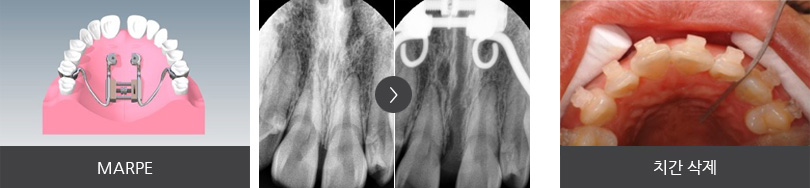

앞니 치열 불규칙하고 어금니가 잘 맞물리지 않아 소리가 나는 증상으로 내원한 22세 대학생입니다.

좌측 위 덧니가 관찰되었고 아래 어금니 배열이 바르지 않아 위 어금니와 정상적인 교합 관계를 보이지 않는

상태였습니다. 이를 빼지 않고 공간을 확보하기 위해 다음의 치료를 진행하였습니다.

앞니 치열이 고르게 개선 되었으며 어금니가 자연스럽게 맞물리는 정상교합이 되었습니다. 자연치아를 빼지 않고

약간의 치간 삭제를 통해 교정 치료가 완료되어 환자 분의 만족도가 높은 케이스였습니다.